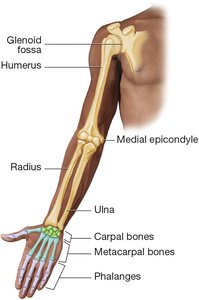

Bones of the Upper Extremity

Shoulder and Arm

The scapula joins the humerus at the glenoid fossa. The acromion of the scapula connects to the clavicle, allowing free movement of the shoulder.

Forearm, Wrist, and Hand

The humerus joins with the radius and ulna. The radius and ulna rotate around each other, allowing the hand to turn. The wrist contains eight carpal bones, the hand has five metacarpal bones, and each finger has three phalanges (except the thumb, which has two).

Bones of the upper extremity including humerus, radius, ulna, carpals, metacarpals, and phalanges